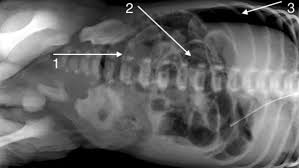

Pediatric Imaging No Twitter Premature Newborn With Abdominal Distension Supine Axr Left Shows Free Air Underneath Diaphragm While Left Lateral Decubitus Axr Right Shows Free Air Between Abdominal Wall Liver And Portal Venous

Pediatric Imaging No Twitter Premature Newborn With Abdominal Distension Supine Axr Left Shows Free Air Underneath Diaphragm While Left Lateral Decubitus Axr Right Shows Free Air Between Abdominal Wall Liver And Portal Venous from pbs.twimg.com